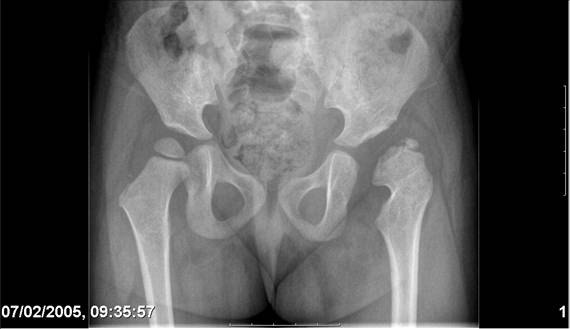

Здравствуйте, уважаемые коллеги.Обратилась девочка 6-ти лет из жалобами на боль в левом т/б суставе,хромоту Из анамнеза : ребенок лечился с рождения по поводу врожденного вывиха бедер. В возрасте 3- х лет в одной из клиник была выполнена остеотомия таза по Пембертону и варизирующая остеотомия бедра слева, справа - остеотомия таза по Солтеру и остеотомия бедра. Посоветуйте тактику лечения. С уважением Ihor

Smotritsya parshivo konechno(pseudoacetabulum,partial AVN), no v6 let ya by popytalsya ispravit chto moghno:shortening (ne boyatsya ubrat bolshoi fragment),derotation(30 gradusov ne bolshe)+pelvic osteotomy in true acetabuluam area.Obyazatelno takghe open reduction with wide capsular exposure.